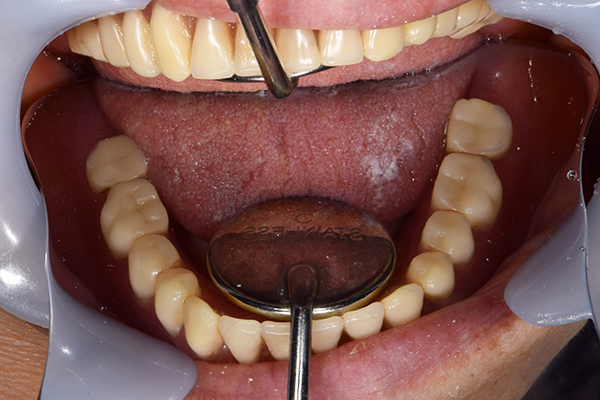

入れ歯をお口の中にいれた状態です。前歯もMTMといって、歯を少し引っ張り出す処置を行なったことで、しっかり残せて、またかぶせ物をしました。

お口の中に入れた状態です。 見た目も最初とほとんど変わることなく作成できました。 維持や吸着に関しても問題ないようでした。

入れ歯を入れた状態のお口の中の写真です。バネも極力目立たないように作成しています。

お口の中に入れた状態です。 非常に見た目もよい出来となりました。 バネがみえないと見栄えが全然ちがいます。